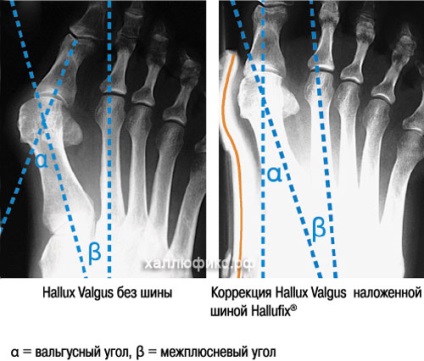

Deplasarea a piciorului forme comune umflaturi neatractivitatea degetele de la picioare mari. Valgus articulat autobuz Hallufix. Ea Hallyufiks chips-uri, dezvoltat de oamenii de stiinta si chirurgii ortopedice pentru a reduce sarcina pe articulația degetului mare și durerea în degetul mare în timp ce mersul pe jos. Se corectează articulația degetului mare atunci când tura (termenul medical: Hallux valgus).

Principiul de funcționare al autobuz Hallufix valgus

atelă ortopedice Hallyufiks revine treptat la forma piciorului naturale, protejează și reduce Hallux valgus. Prin banda au redus curbura degetului mare, a extins țesutul muscular al articulației de bază mare deget de la piciorul, și există o corecție comună în timp ce mersul pe jos.

Datorită metatarsian bandaj dispozitiv înfășurați picior și deget de la picior, sarcina reglată de degetul mare, care este, cu ajutorul piciorului de anvelope predispuse Hallux valgus, se poate indoi in mod natural si fara durere.

În plus, suportul transversal metatarsian arc ajută la restabilirea arcului (arc transversal al piciorului) în jurul axei verticale. Oprește Offset autobuz valgus exterior sprijinit perfect. Bandaj combină funcția comună de deplasare corective și funcția de corectare a arcului transversal a piciorului.